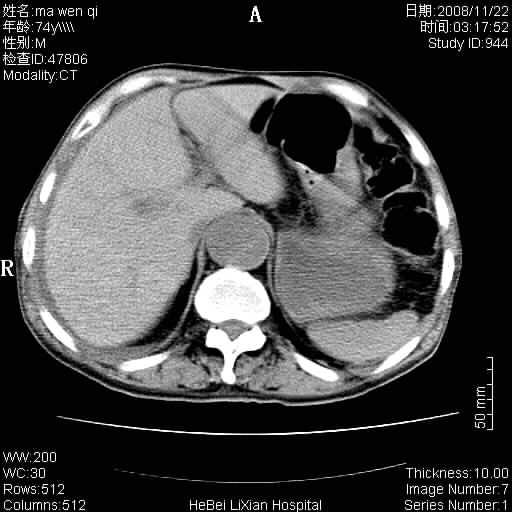

患者男 74岁.突然昏迷,休克6小时.血压70/30,头颅ct未见异常,既往体健.

补充病史,保留导尿10小时,尿袋内只有少许尿液,患者于住院后15小时后去世.

腹主动脉、双侧髂动脉夹层动脉瘤破裂出血进入腹腔。

1)考虑双侧髂动脉瘤并右侧动脉瘤破裂出血,右侧腹膜后及腹腔积血。2)双侧腹股沟疝。

1)考虑,腹主动脉、双侧髂动脉夹层动脉瘤破裂伴右侧腹膜后及腹腔积血。2)双侧腹股沟疝。

1)考虑胸、腹主动脉、双侧髂动脉瘤并右侧动脉瘤破裂出血,右侧腹膜后及腹腔积血。2)双侧腹股沟疝。